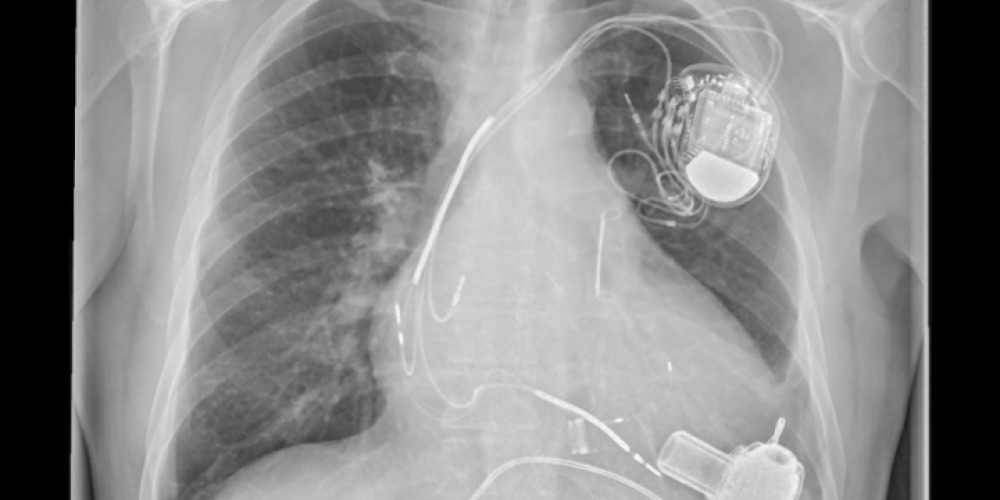

Foutieve dosering van geneesmiddelen in medicijnenpomp kan fataal aflopen